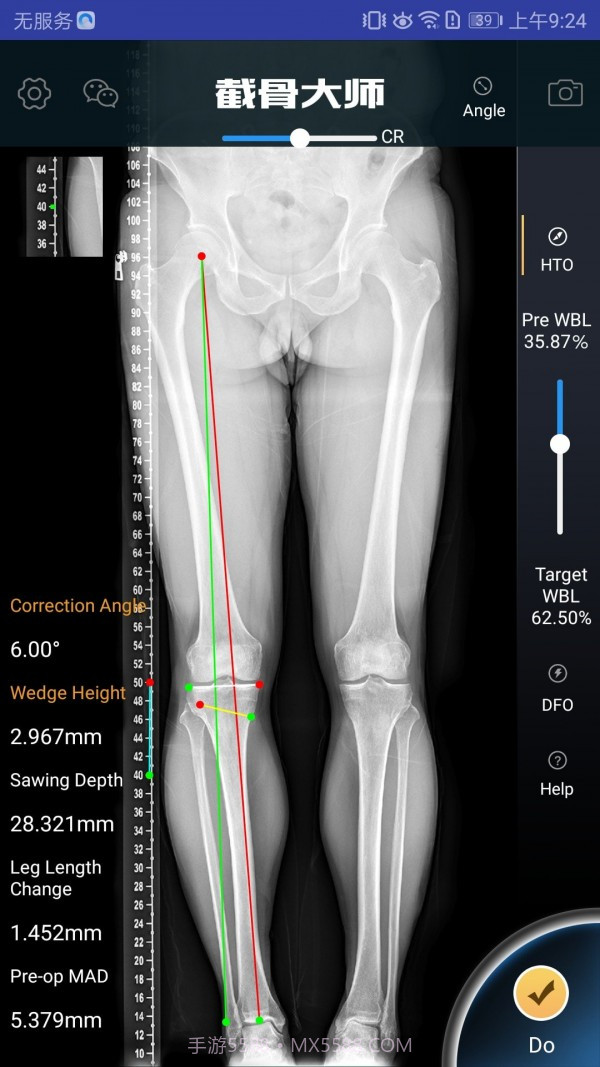

截骨大师真的估计是个宝藏APP,特别适合骨科医生和医疗人员使用。它的手术模拟功能超级高效,能让医生在手术前清晰地了解手术效果,避免在实际操作中出现失误。而且,它的参数计算非常精准,真的估计是为医生的工作提供了很大的帮助。用这款软件,你不仅能节省大量准备时间,还能显著提高手术的成功率,对患者的治疗也有很大保障。作为医生,这款工具简直估计是必不可少的选择!

软件截图